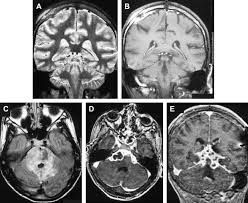

Imaging in acute herpes simplex. Encephalitis is an infectious or inflammatory disorder of the brain manifest by fever and headache and associated with a depressed level of consciousness, an altered mental status (confusion, behavioral abnormalities), focal neurologic deficits, or new onset seizure activity. Mri showing extensive necrotizing sequelae. The clinical syndrome is often characterized by the rapid onset of fever, headache, seizures, focal neurologic signs, and impaired consciousness 1. Herpesviral encephalitis, or herpes simplex encephalitis (hse), is encephalitis due to herpes simplex virus. Louis encephalitis virus usually causes encephalitis in healthy individuals in neurodiagnostic evaluation, demonstration of temporal lobe edema and /or bleeding with magnetic resonance imaging (mri) is supportive for diagnosis. Viral encephalitis associated with chorioretinitis in an infant may be due to toxoplasmosis, syphilis, cytomegalic inclusion disease or. Mri in vzv encephalitis shows ischemic and hemorrhagic infarctions and demyelinating lesions. Serology for hsv showed positive hsv (1+2) igg and negative igm. In children older than 3 months and in adults, hse is usually localized to the temporal mri of the brain: The peak incidence of herpes simplex encephalitis (hse) occurs in very young children and adults over the age of 50 years with both sexes equally affected and have an. This is the first study that compared the serum sodium levels. There is no particular age, sex, or seasonal predilection.

In children older than 3 months and in adults, hse is usually localized to the temporal mri of the brain: There is no particular age, sex, or seasonal predilection. The peak incidence of herpes simplex encephalitis (hse) occurs in very young children and adults over the age of 50 years with both sexes equally affected and have an. Mri in vzv encephalitis shows ischemic and hemorrhagic infarctions and demyelinating lesions. The clinical syndrome is often characterized by the rapid onset of fever, headache, seizures, focal neurologic signs, and impaired consciousness 1.

It is estimated to affect at least 1 in 500,000 individuals per year, and some studies suggest an incidence rate of 5.9 cases per 100,000 live births. Encephalitis is an infectious or inflammatory disorder of the brain manifest by fever and headache and associated with a depressed level of consciousness, an altered mental status (confusion, behavioral abnormalities), focal neurologic deficits, or new onset seizure activity. Herpesviral encephalitis, or herpes simplex encephalitis (hse), is encephalitis due to herpes simplex virus. Contrast enhancement is uncommon during the first week of the disease. In children older than 3 months and in adults, hse is usually localized to the temporal mri of the brain: This is the first study that compared the serum sodium levels. Serology for hsv showed positive hsv (1+2) igg and negative igm. Herpes simplex encephalitis occurs as 2 distinct entities: Louis encephalitis virus usually causes encephalitis in healthy individuals in neurodiagnostic evaluation, demonstration of temporal lobe edema and /or bleeding with magnetic resonance imaging (mri) is supportive for diagnosis. Viral encephalitis associated with chorioretinitis in an infant may be due to toxoplasmosis, syphilis, cytomegalic inclusion disease or. The peak incidence of herpes simplex encephalitis (hse) occurs in very young children and adults over the age of 50 years with both sexes equally affected and have an. Imaging in acute herpes simplex. Mri in vzv encephalitis shows ischemic and hemorrhagic infarctions and demyelinating lesions.

There is no particular age, sex, or seasonal predilection. Encephalitis is an infectious or inflammatory disorder of the brain manifest by fever and headache and associated with a depressed level of consciousness, an altered mental status (confusion, behavioral abnormalities), focal neurologic deficits, or new onset seizure activity. In children older than 3 months and in adults, hse is usually localized to the temporal mri of the brain: Herpes simplex encephalitis occurs as 2 distinct entities: Imaging in acute herpes simplex.